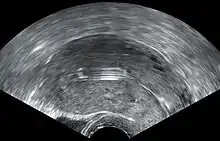

Schematic depiction of vaginal ultrasonography of a Mirena.

Vaginal ultrasonography showing a Mirena in optimal place in the uterus, as viewed from angle shown in schematic depiction.